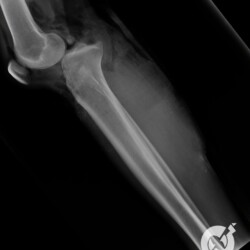

Fratura da patela com importante desvio e fratura cominutiva do 1/3 proximal da tíbia comprometendo a eminência intercondiliana.